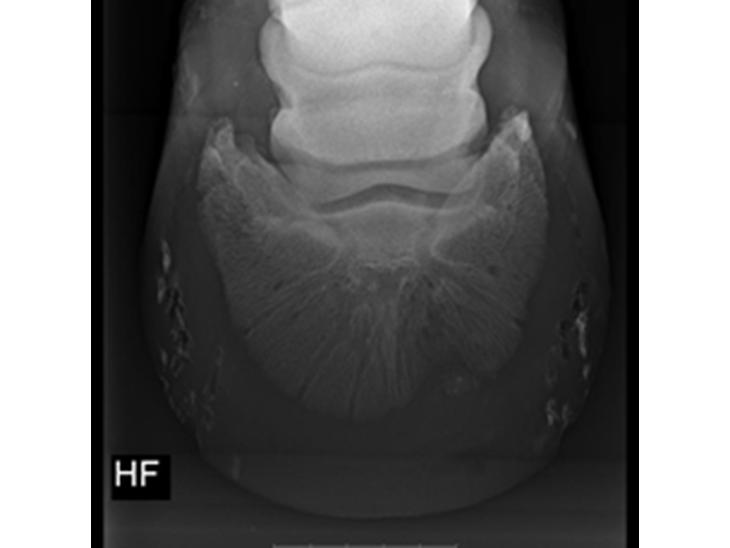

Silvas hov operation (keratom)

Dette er billeder fra Silva blev opereret i hoven d. 10/5-16 og til i dag 16/9-16.

Det er en lidelse som mange ikke har hørt om, inkl mig selv. Så da Silva fik denne diagnose savnede jeg information og erfaringer fra andre heste ejere. Så jeg håber mit foto album kan bidrage med viden til andre der måske kommer i samme situation.